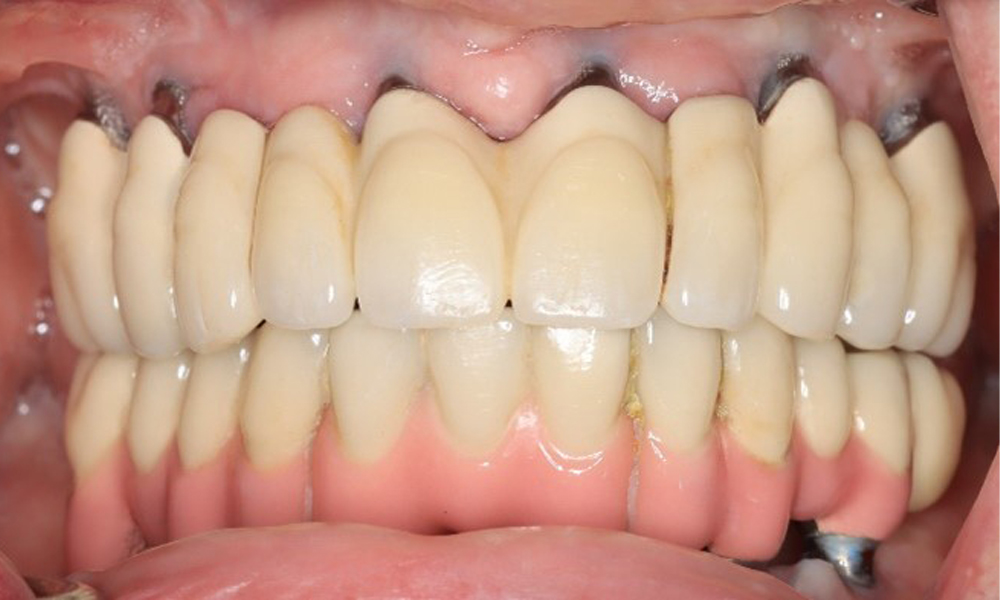

Frontansicht Gebiss (Ober- und Unterkiefer)

Abb. 3: Frontansicht

Eine 74-jährige Patientin stellt sich in der Sprechstunde vor. Die Anamnese zeigt, dass die Patientin gut eingestellten Bluthochdruck hat und Lixiana einnimmt. Weiterhin hatte die Patientin im Jahr 2020 ein Nierenkarzinom. Die Lebensgewohnheiten der Patientin sind unauffällig. Die Patientin hat keine eigenen Zähne mehr. Sie hat im Oberkiefer und Unterkiefer jeweils sechs Implantate, die mit Kronen bzw. über Brücken versorgt sind. Anhand der aktuellen Befunde lässt sich keine periimplantäre Mukositis bzw. Periimplantitis feststellen; vereinzelte (geringfügige) Blutungen an den Implantat(-versorgungen) liegen vor.

Versorgungen: Implantate regio 011, 013, 015, 021, 023, 025, 031, 033, 035, 042, 044, 046